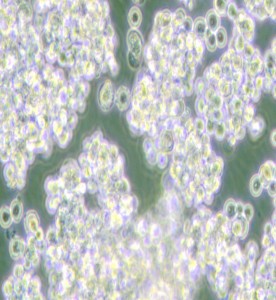

NCI-H524人小細胞肺癌細胞

細胞形態 : 圓形

生長特性 : 懸浮細胞